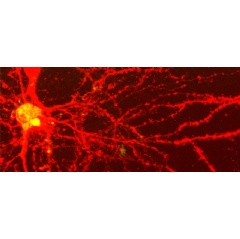

In a study published online in Science Advances, Vladislav Verkhusha, Ph.D., and colleagues used a genetically encoded reversibly switchable bacterial phytochrome (RSBP) as a guide star for focusing light at specific locations in cells deep within living mice. The light could penetrate deeply into tissues because RSBPs work at the near-infrared (NIR) portion of the light spectrum, where photons are least interfered with by surrounding tissue.

The researchers used the technique to successfully focus on cells within tumors and brain tissue in living mice. The technique may be especially helpful in extending the range of photodynamic therapy (which chemically renders cells vulnerable to NIR light) to treat tumors deep inside the body. Dr. Verkhusha is professor of anatomy and structural biology and the Gruss Lipper Biophotonics Center at Einstein.